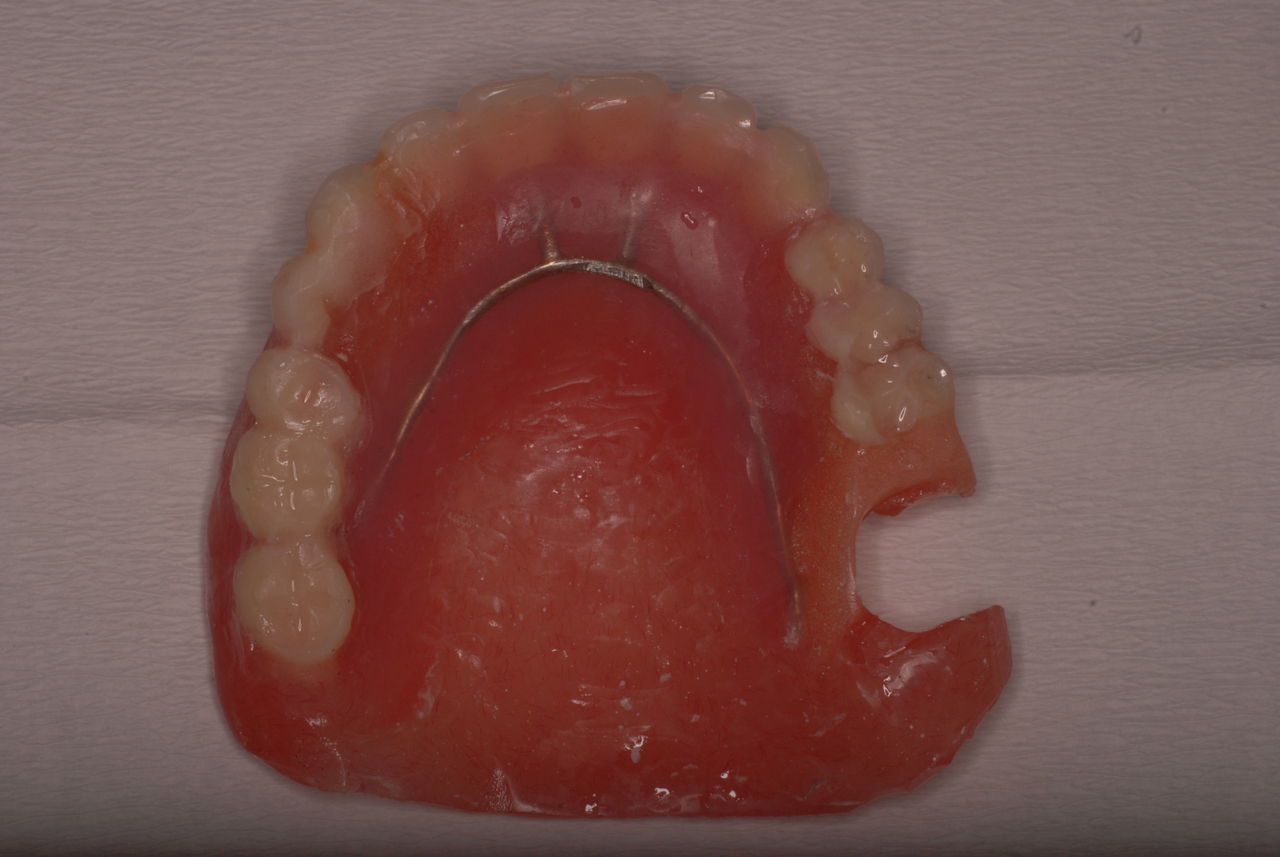

写真の方の高額な入れ歯を拝見するとまず喉の方向の入れ歯の位置が悪く吸着できていない。クラスプと言われる金属の歯を掴むものの形と材料も?でした。全体的に入れ歯のマージンを頬の筋肉で保持できるような形にできていないために吸着が悪いのです。

ですから、全然使用していない安い保険の義歯を使い修理して動かず、痛まず、咬めるようにしてあげると信用絶大になるのです。

写真の入れ歯はボロボロの保険の入れ歯を何とか修理してお渡ししたものです。その後電話で尋ねましたが痛くもなく初めてご飯を食べられるようになったということでした。